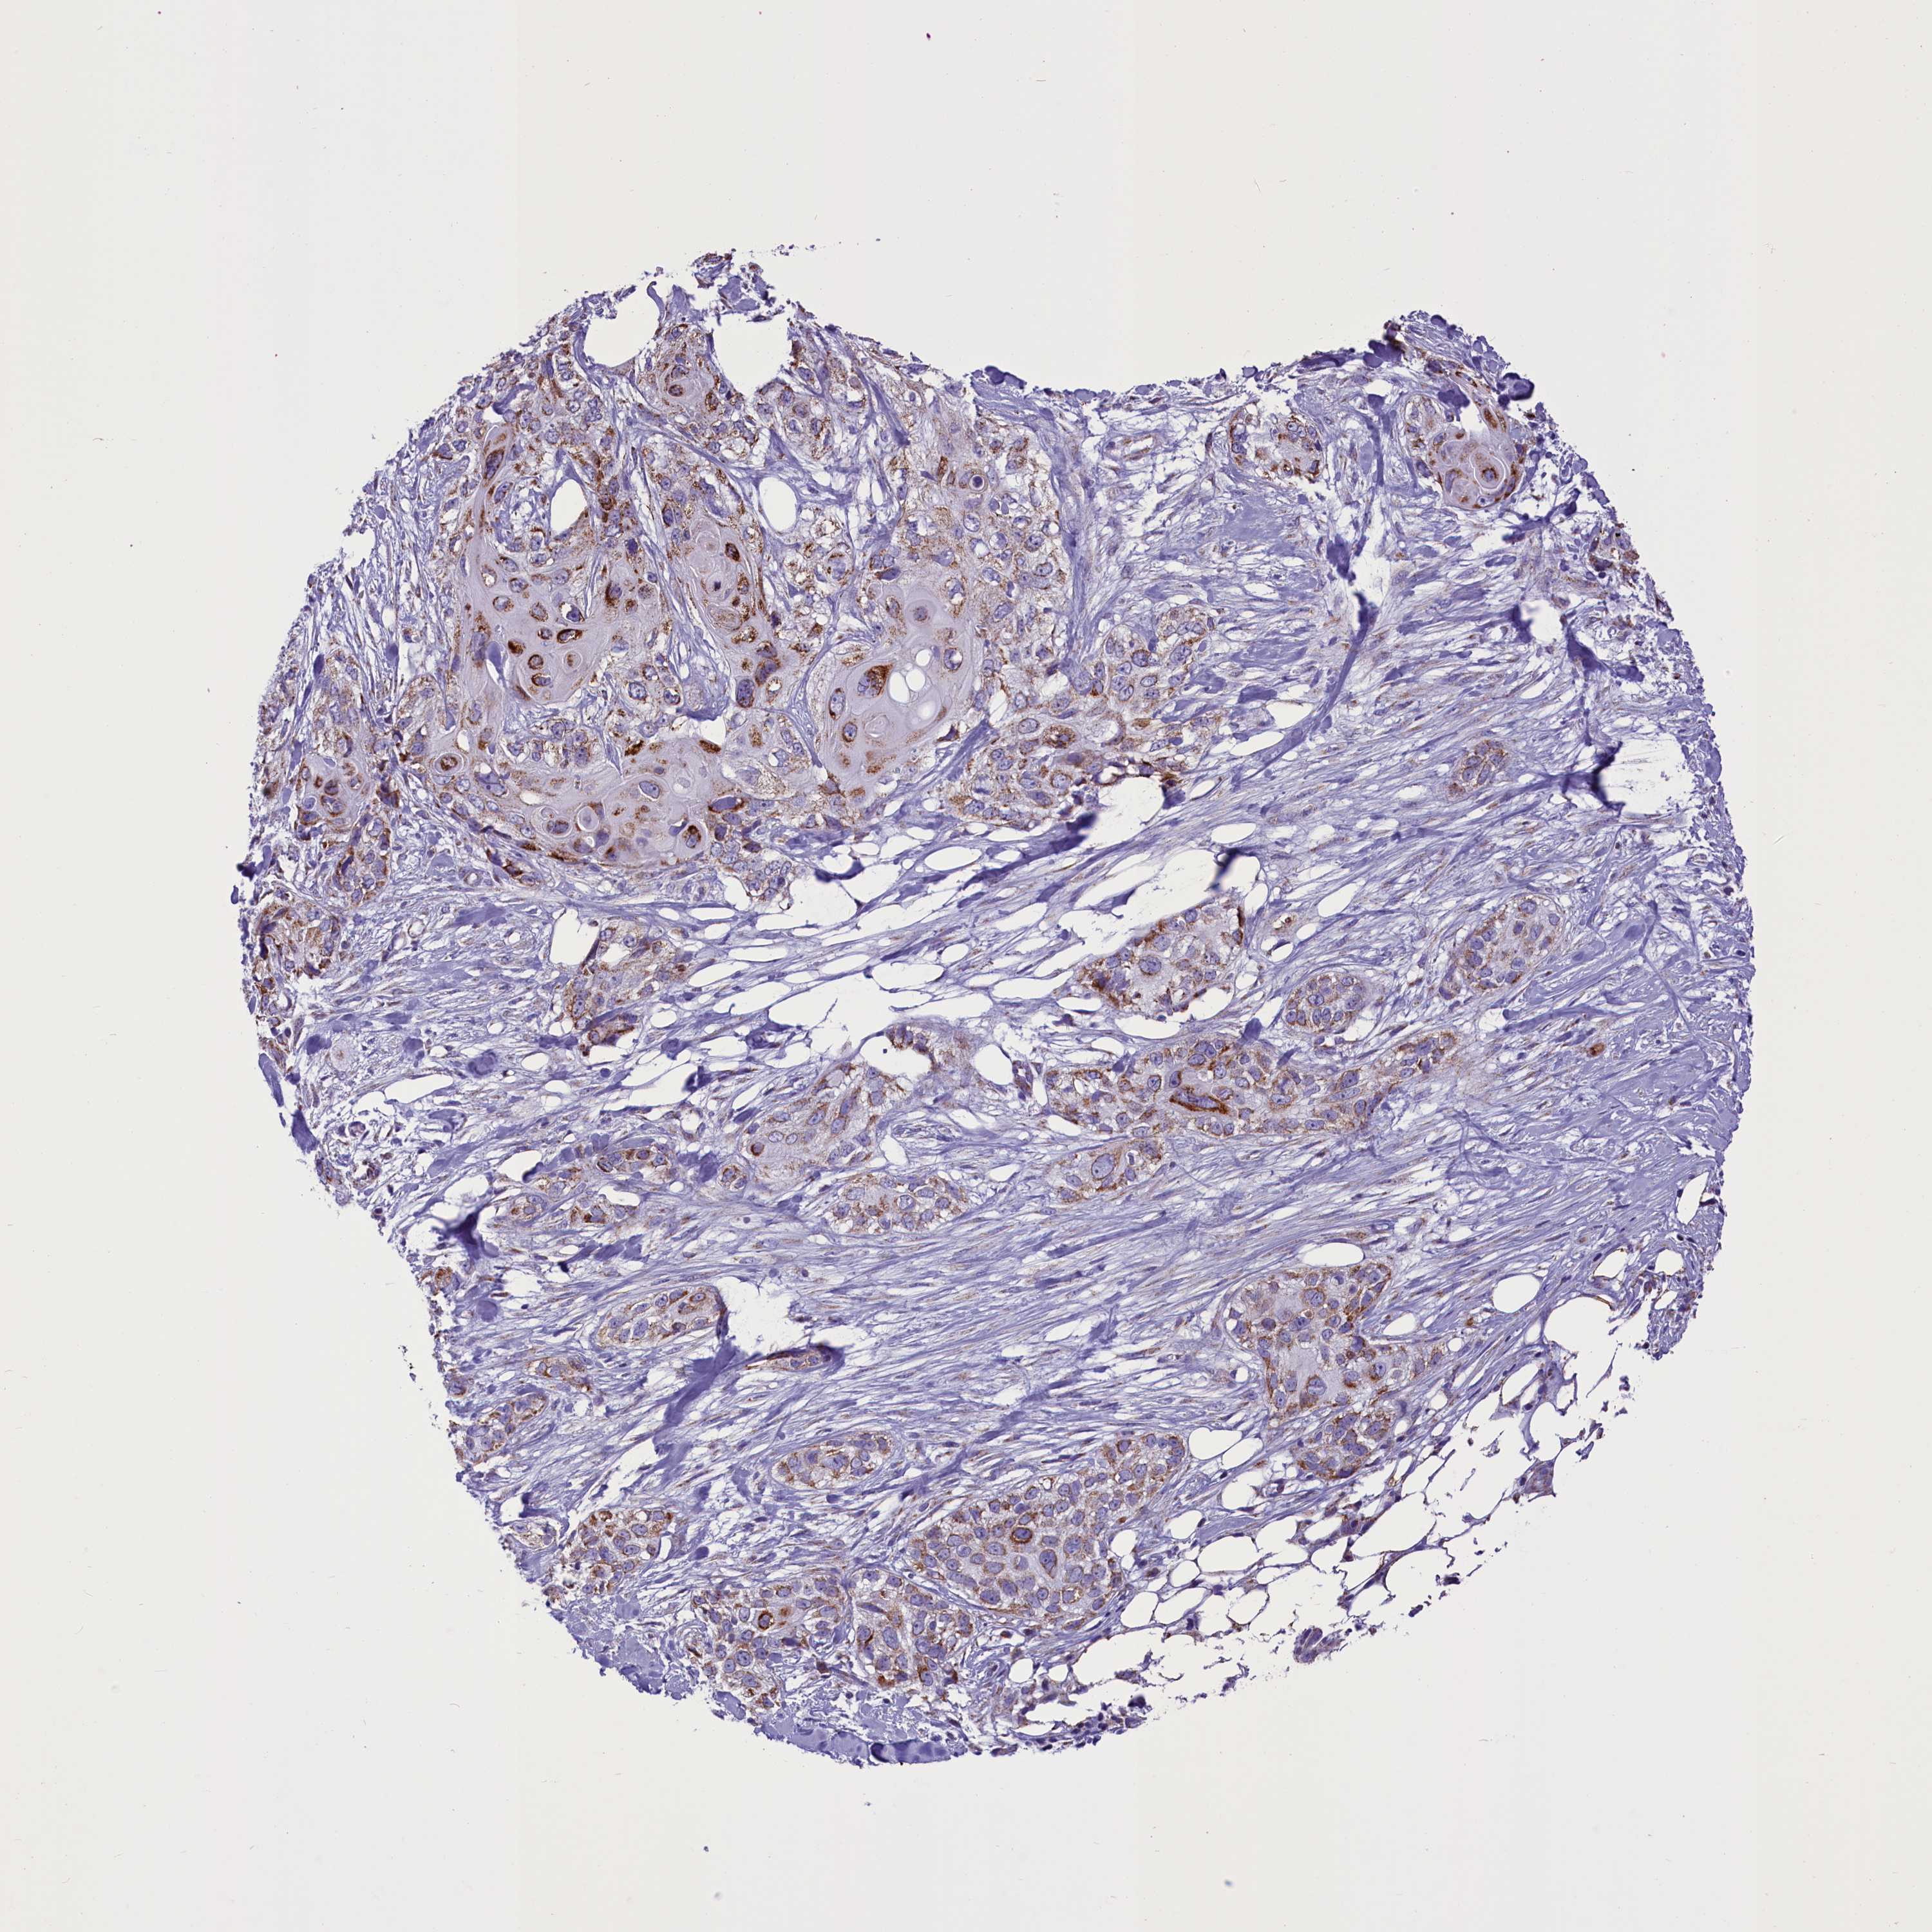

SKIN CANCER - Protein expressioni

A mouse-over function shows sample information and annotation data. Click on an image to view it in a full screen mode. Samples can be filtered based on level of antibody staining by selecting one or several of the following categories: high, medium, low and not detected. The assay and annotation is described here.

Antibody stainingi

Antibody staining in the annotated cell types in the current human tissue is reported as not detected, low, medium, or high, based on conventional immunohistochemistry profiling in selected tissues. This score is based on the combination of the staining intensity and fraction of stained cells.

Each image is clickable and will lead to virtual microscopy that enables deeper exploration of all samples and also displays staining intensity scores, fraction scores and subcellular localization as well as patient and tissue information for each sample.

Antibody HPA042507

Staining

High

Medium

Low

Not detected

Intensity

Strong

Moderate

Weak

Negative

Quantity

>75%

75%-25%

<25%

None

Location

Nuclear

Cytoplasmic/membranous

Cytoplasmic/membranous,nuclear

Basal cell carcinoma